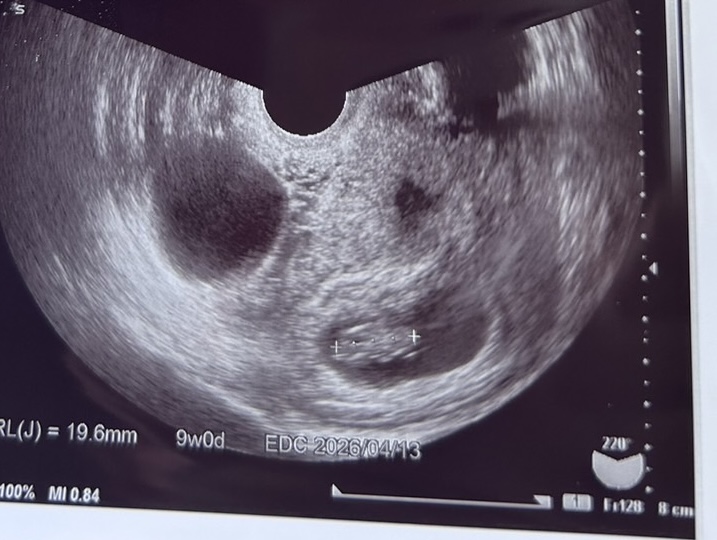

妊娠9週の時のエコーです。胎嚢が二つあるように見えるのですが、9週の時点で空に見えるので出血しているのか。診察時は緊張して色々聞けませんでしたが、時間が経つにつれ気になってきてしまいました。

この左の黒い影は胎嚢なのでしょうか?出血なのでしょうか?

お写真、拝見させていただきました。ママさんが気になる黒いものは、左側の大きなものでしょうか?それとも胎嚢上にある小さな黒いものでしょうか?

いずれにせよ、胎嚢のような感じにはお見受けできないです。

出血であるかの断言も珍しく、啓蟄エコーの向きにもよりますが、大きいものは膀胱(尿)かもしれません。

医師から、指摘がない場合、心配なものである可能性は高くないと思います。

左側の大きな影が気になっておりました。

尿もこのようにエコーに映るのですね。胎嚢ならそれは嬉しいし、出血であれば心配なので落ち着かずにおりましたが、正体がわかって安心しました。